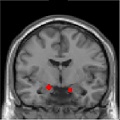

This study has shed light on the neurocomputational contributions to the development of post-traumatic stress disorder in combat veterans, finding distinct patterns for how the brain and body respond to learning danger and safety depending on the severity of PTSD symptoms.